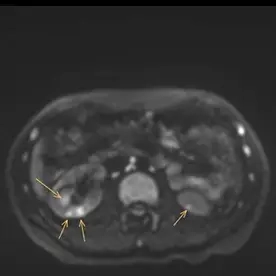

Es erfolgte eine MRT der Nieren mit intravenöser Kontrastmittelgabe und urographischer Phase zur dedizierten Darstellung der ableitenden Harnwege. Es bestätigte sich eine Anlagevariante der rechten ableitenden Harnwege, eine Doppelung des rechten proximalen Ureters mit Fusion im proximalen Drittel (Ureter fissus) bei regelrechter Darstellung der Nierenbeckenkelchsysteme (Bild 1). Im Nierenparenchym beidseits zeigen sich mehrere, keilförmige Areale mit Diffusionsstörungen und teils T2-hyperintensen Foci (Bild 2 und 3). Nach i.v. Kontrastmittelgabe zeigt sich ein weitesgehend unauffällig und homogen kontrastiertes Nierenparenchym beidseits (Bild 4).

Bild einer chronischen Pyelonephritis i.R. einer rezidivierender Reflux auf dem Boden eines Ureter fissus.